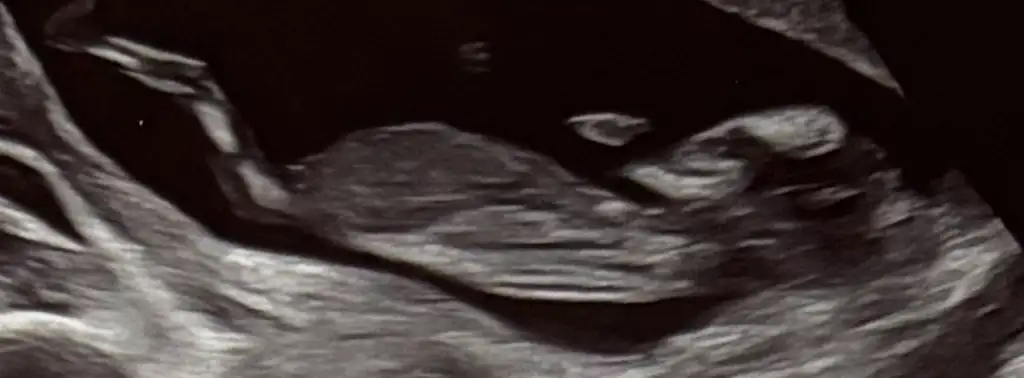

Kızlar bu ultrason görüntülerinden ben hiçbir şey anlayamıyorum, siz nasıl anlıyorsunuz ya 🙈 bunların açısı falan mı farklı olmalı anlayabilmek için, yoksa cinsiyet yorumu olan var mı? Chatgpt ye attım yorum yapmıyor, başka açıdan çekilmeli diyor. 12+0da çekildi bu görüntüler. Biz fetal dna yaptırdık ama yaptırdığımız yer yeditepe ünv hastanesi ve cinsiyet bilgisi paylaşmıyormuş. O yüzden oradan da öğrenemeyeceğim.

Ben kız diyorum çıkıntı olan yer daha yukarıda olsa erkek derdim bir de bacak arası gördüm sanki ve orası da boş :)